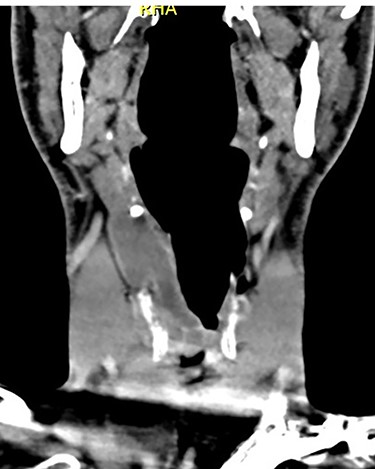

Coronal CT of neck showing the internal and external components of the laryngocoele, in relation to the thyrohyoid membrane.

On examination, he was tachypnoeic, with a respiratory rate of 32 and oxygen saturations of 92% on room air. Although he was afebrile and haemodynamically stable, he was visibly exhausted, with accessory muscle use and stridulous breathing. There were no palpable swellings in the patient’s neck. Flexible nasoendoscopy showed a large submucosal swelling arising from the right vestibular fold, causing intermittent airway obstruction (Video) (Fig. 2). Laboratory markers were within normal range. Computed tomography of neck showed a well-defined, peripherally enhancing collection in right paraglottic space, extending from level of hyoid bone into the right laryngeal ventricle, with significant airway compromise at the level of the vocal cords (Figs 3 and 4).